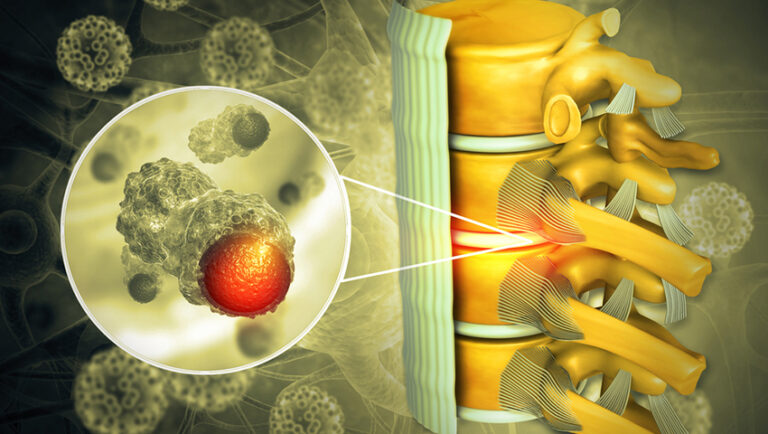

درمان سرطان ستون فقرات گاهی اوقات شامل جراحی میشود. هدف از جراحی سرطان ستون فقرات به عوامل مختلفی از جمله محل و درجه تومور و علائم موجود بستگی دارد. زمانی که تومور به یک قسمت از ستون فقرات محدود میشود، ممکن است جراحی را برای برداشتن سرطان انجام دهید....